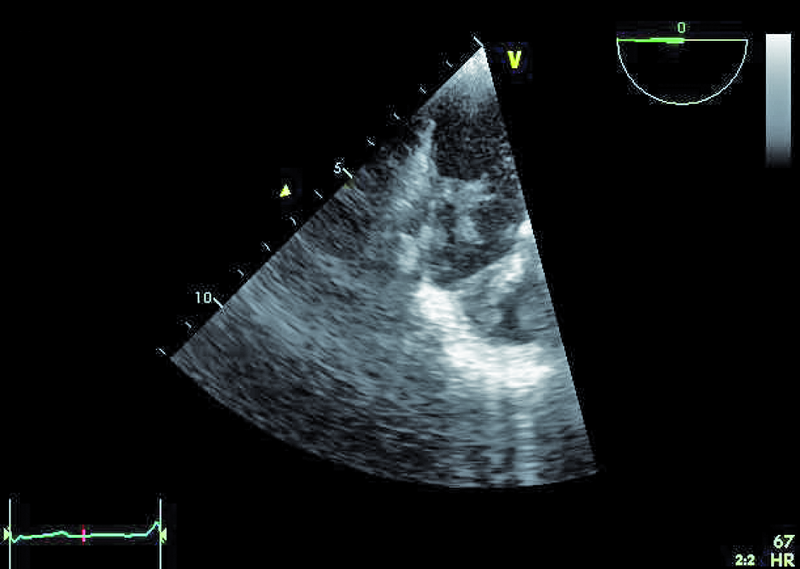

Mężczyzna, lat 25. Jakie patologie można rozpoznać na rycinach?

2. Dodatkowe echa (skrzepliny, wegetacje?) związane z elektrodą (ryc. 2).